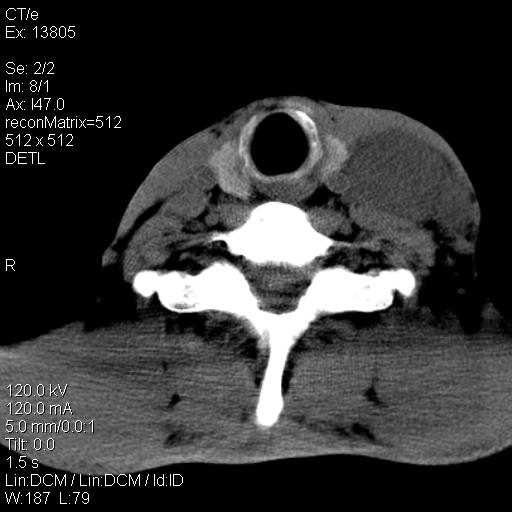

上腹部疼痛一月,呕吐10天,发现左侧颈部包快10天 胸部cr片未见明显异常。

左侧胸锁乳突肌下方、颈血管旁低密度肿块影,肿块密度尚均匀,边缘大部分清楚,邻近组织稍受压移位。考虑颈部神经鞘瘤可能性大。